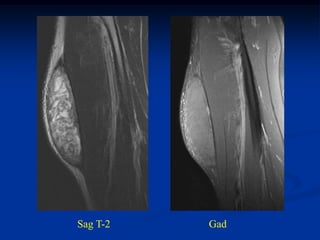

Case #250.3      Sag T-2                 Sag Gad

15 year female with painful enlarging desmoid past 6 months

while on chemotherapy

Coronal Gad shows minimal response to chemotherapy